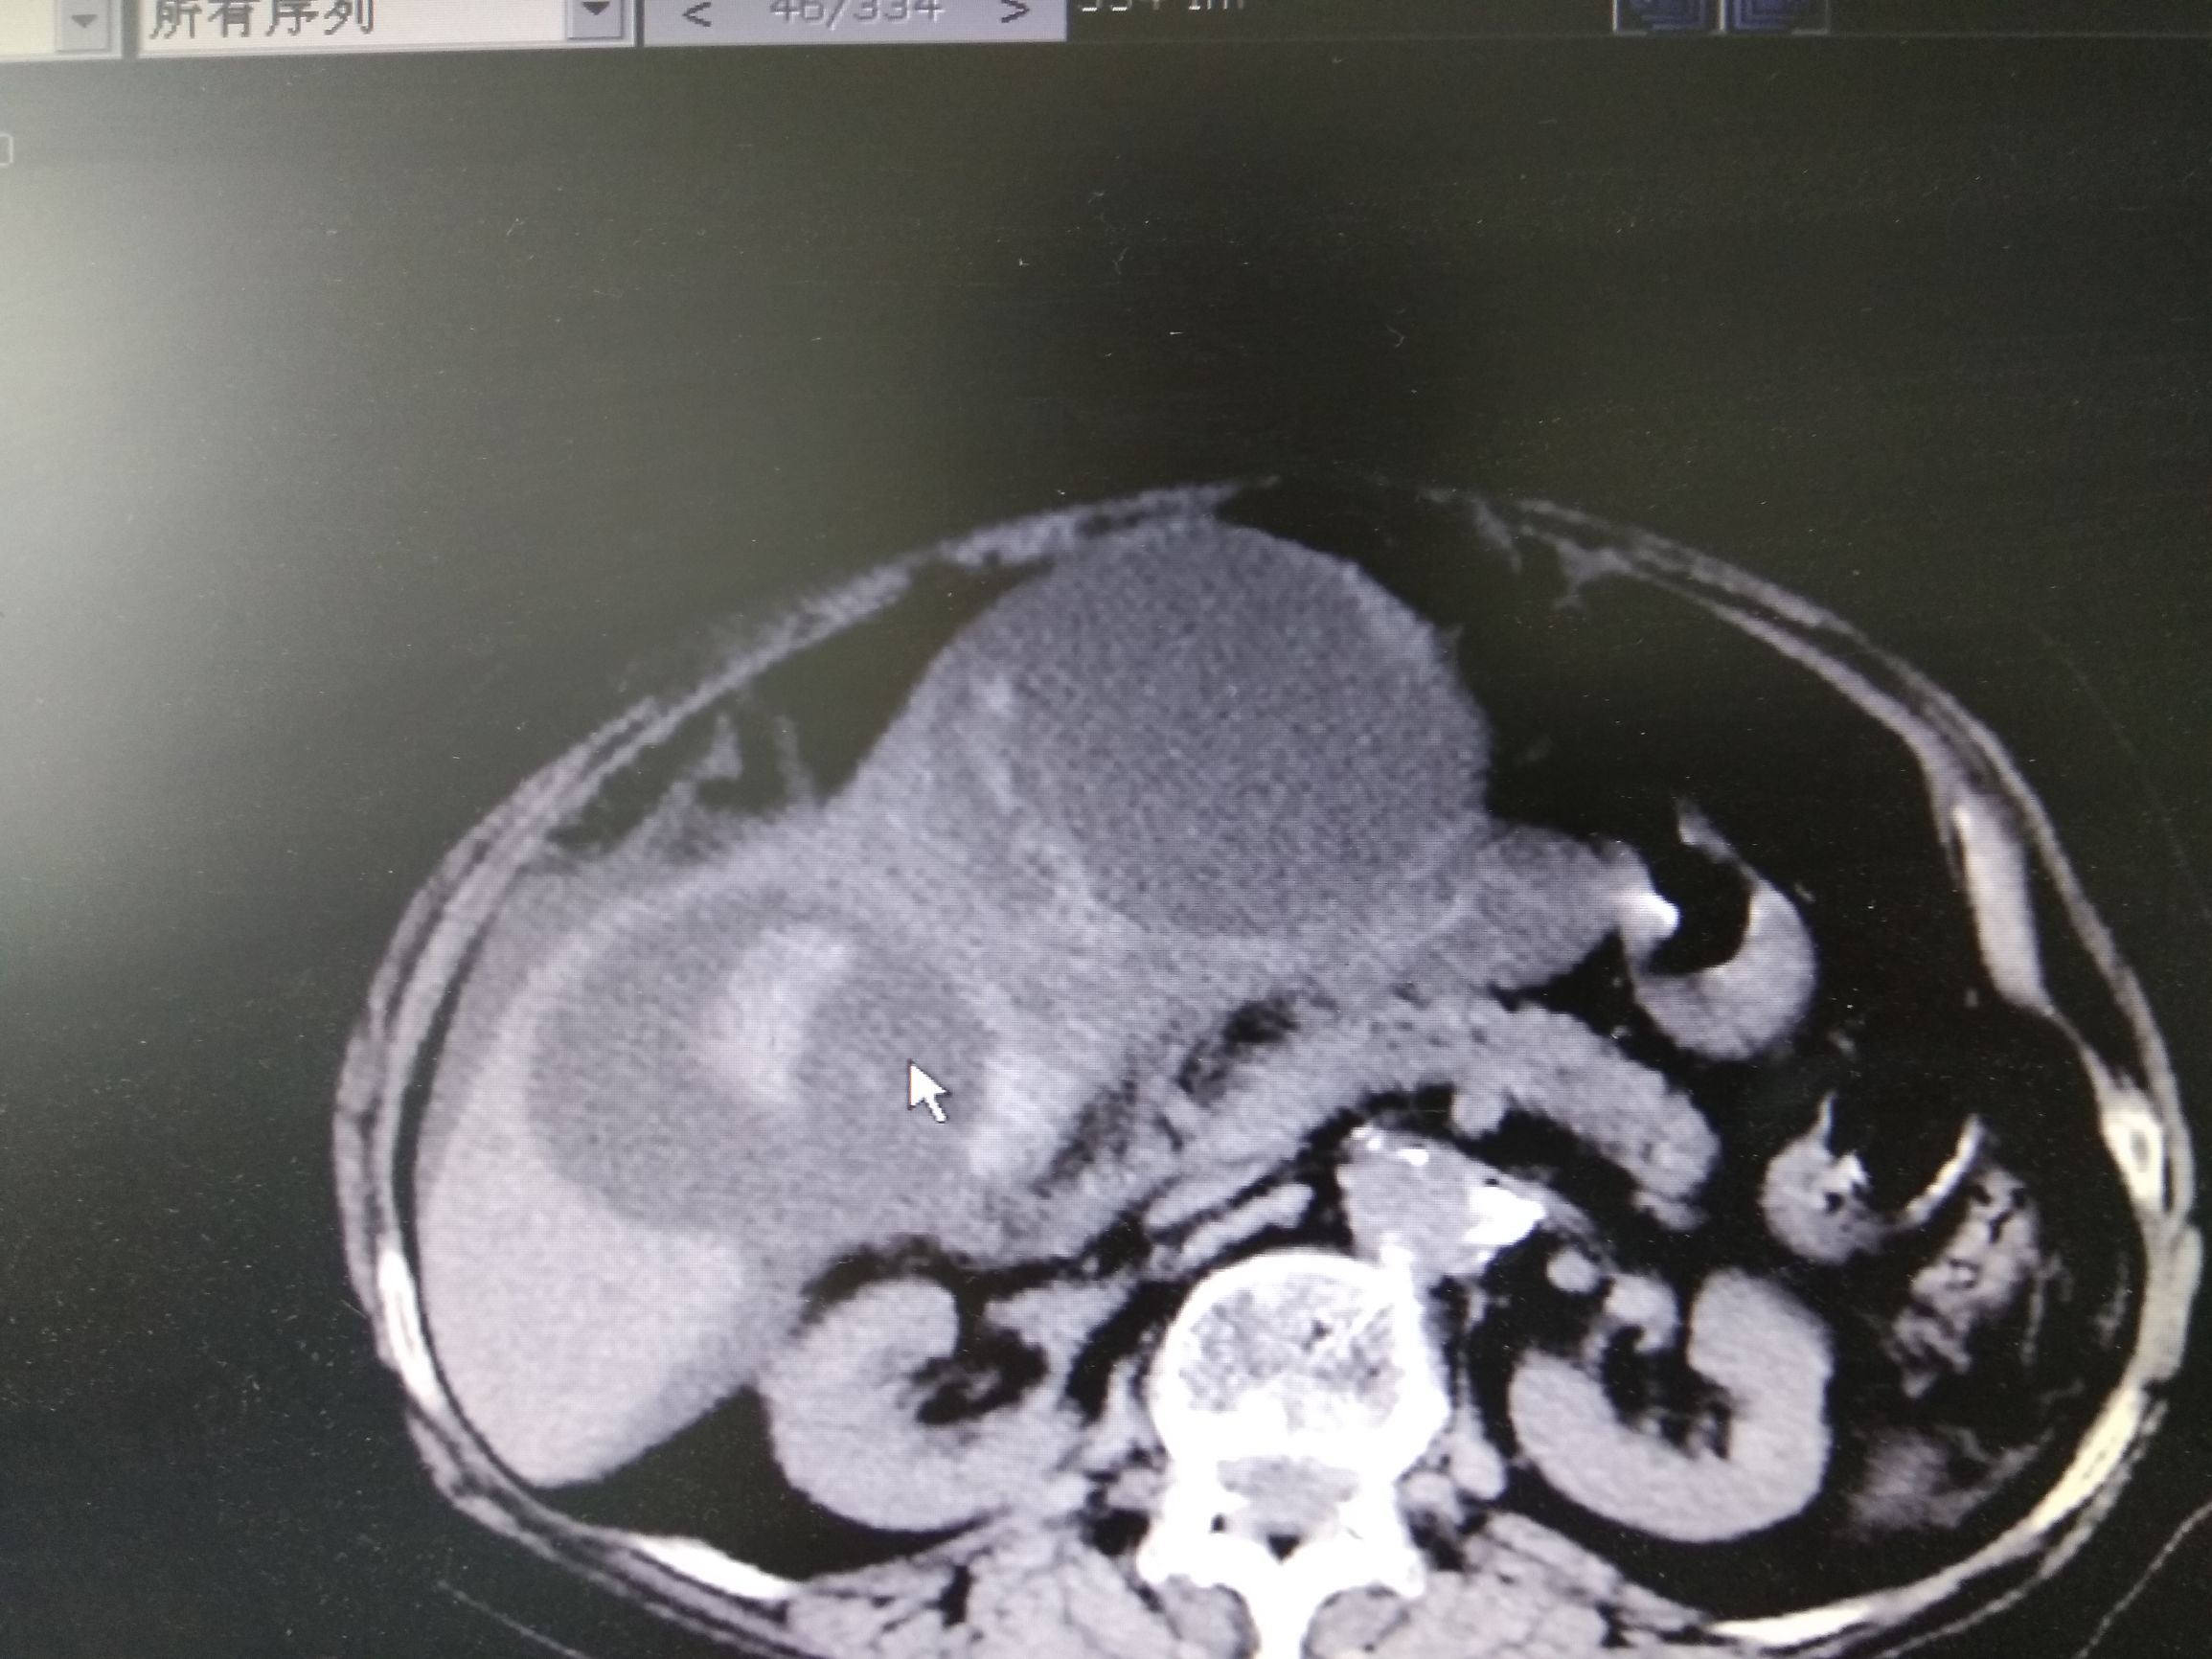

可是过了不到一个月李奶奶再次出现了腹胀,并且伴有发热,李奶奶再次来到了医院,医生复查CT,CT结果囊肿又变大了,而且囊肿里面有高密度,医生解释那有可能是出血,于是李奶奶再次做了穿刺抽液,抽出来的是血性混浊的液体,但是过了几天再次复查积液又多了,而且发热症状不缓解,这时候医生开始怀疑病人的疾病可能不是简单的肝囊肿,做了肝脏强化CT检查,并且检查了肿瘤标记物,CA199,CEA升高,在查阅很多文献,以及请相关专家会诊以后考虑李奶奶这个病就是肝脏囊腺癌,是一种比较少见的肝脏癌症。

胆管囊腺癌为一种少见的原发于肝脏的囊性恶性肿瘤。一般认为是源于肝内胆管上皮细胞的囊腺瘤恶变引起。胆管囊腺癌呈囊状,囊内壁被覆黏液上皮,上皮常形成大小不等的乳头状赘生物突起,少数有点状钙化灶。囊液为淡黄色或棕黄色黏性胶冻样液体。当伴有出血和感染时,囊液可呈血性或脓性。囊腺癌以单发性多囊腔为特征,偶为多发性单囊腔。光镜检查囊壁内衬以恶变的胆管上皮细胞,间隔为纤维组织。